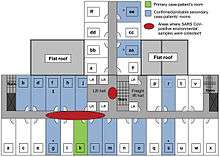

Another larger cluster of cases in Hong Kong centred on the Amoy Gardens housing estate. Its spread is suspected to have been facilitated by defects in its drainage system. Concerned citizens in Hong Kong worried that information was not reaching people quickly enough and created a website called sosick.org, which eventually forced the Hong Kong government to provide information related to SARS in a timely manner.[26]